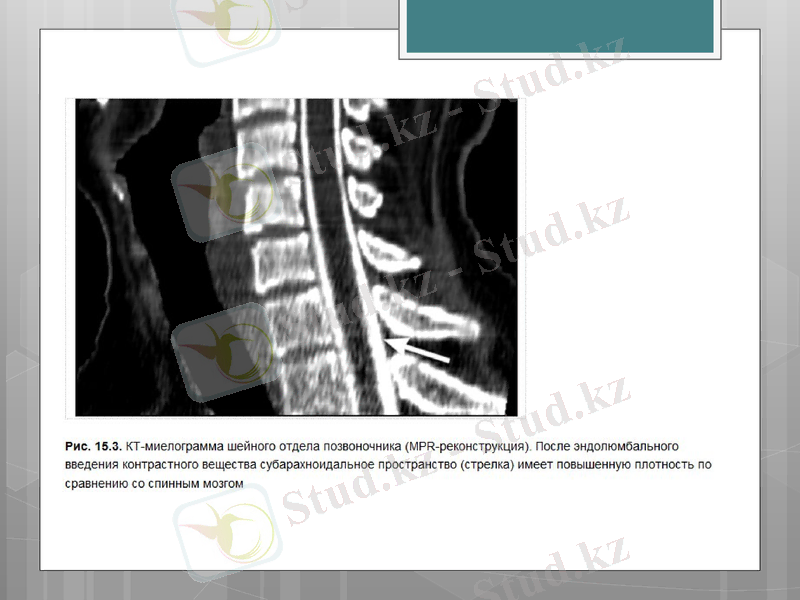

КТ сканирлеудің барлық қашықтығында омыртқаның әртүрлі құрылымдарының қабаттық көріністерін алуға мүмкіндік береді, соның ішінде паравертебральды аймақтың жұмсақ тіндері, трабекулярлы және қыртысты қабаттарымен сүйек құрылымдары, құрамында май тіні бар жұлын өзегі, жұлын, дүйке түйіндері, жұлын-ми сұйықтығы.

Спиральды режимдегі КТ-зерттеу омыртқа жарақаты бар науқастарда диагностиканың қолайлы әдісі болып есептеледі. Сүйек құрылымдарының, аралас мүшелер мен тіндердің барлық анатомиялық өзгерістерін сипаттауға және дуральды қаптың жағдайын бағалауға болады.